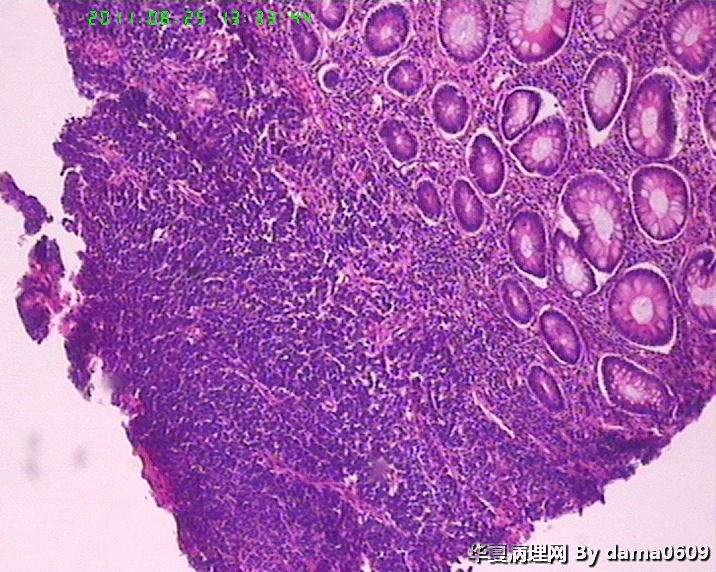

患者男性,39岁。以回盲部肿物行肠镜检查、活检。镜下四块组织内有两块见呈巢状的小细胞(如图

),另两块为粘膜慢性炎表现及坏死组织。学生不知如何分类:未分化癌?类癌?小细胞癌?请老师指教。谢谢!

细胞核较小、深染、一致,核分裂象少见,支持典型类癌。

神经内分泌肿瘤 淋巴瘤 低分化腺癌。。。

神经内分泌肿瘤

楼主是想说“未分化癌”?片子切的比较厚,考虑神经内分泌肿瘤,低分化腺癌待排。

神经内分泌肿瘤?低分化腺癌?标一下神经内分泌标记

高级别癌,活检标本,可做IHC先排除高级别神经内分泌肿瘤。

如果神经内分泌阴性,明确分型等手术根治标本。